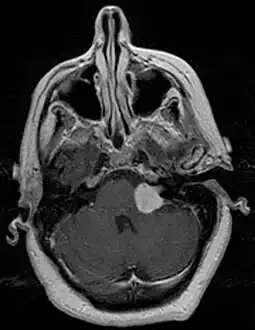

Bilateral schwannomas in a person with neurofibromatosis 2